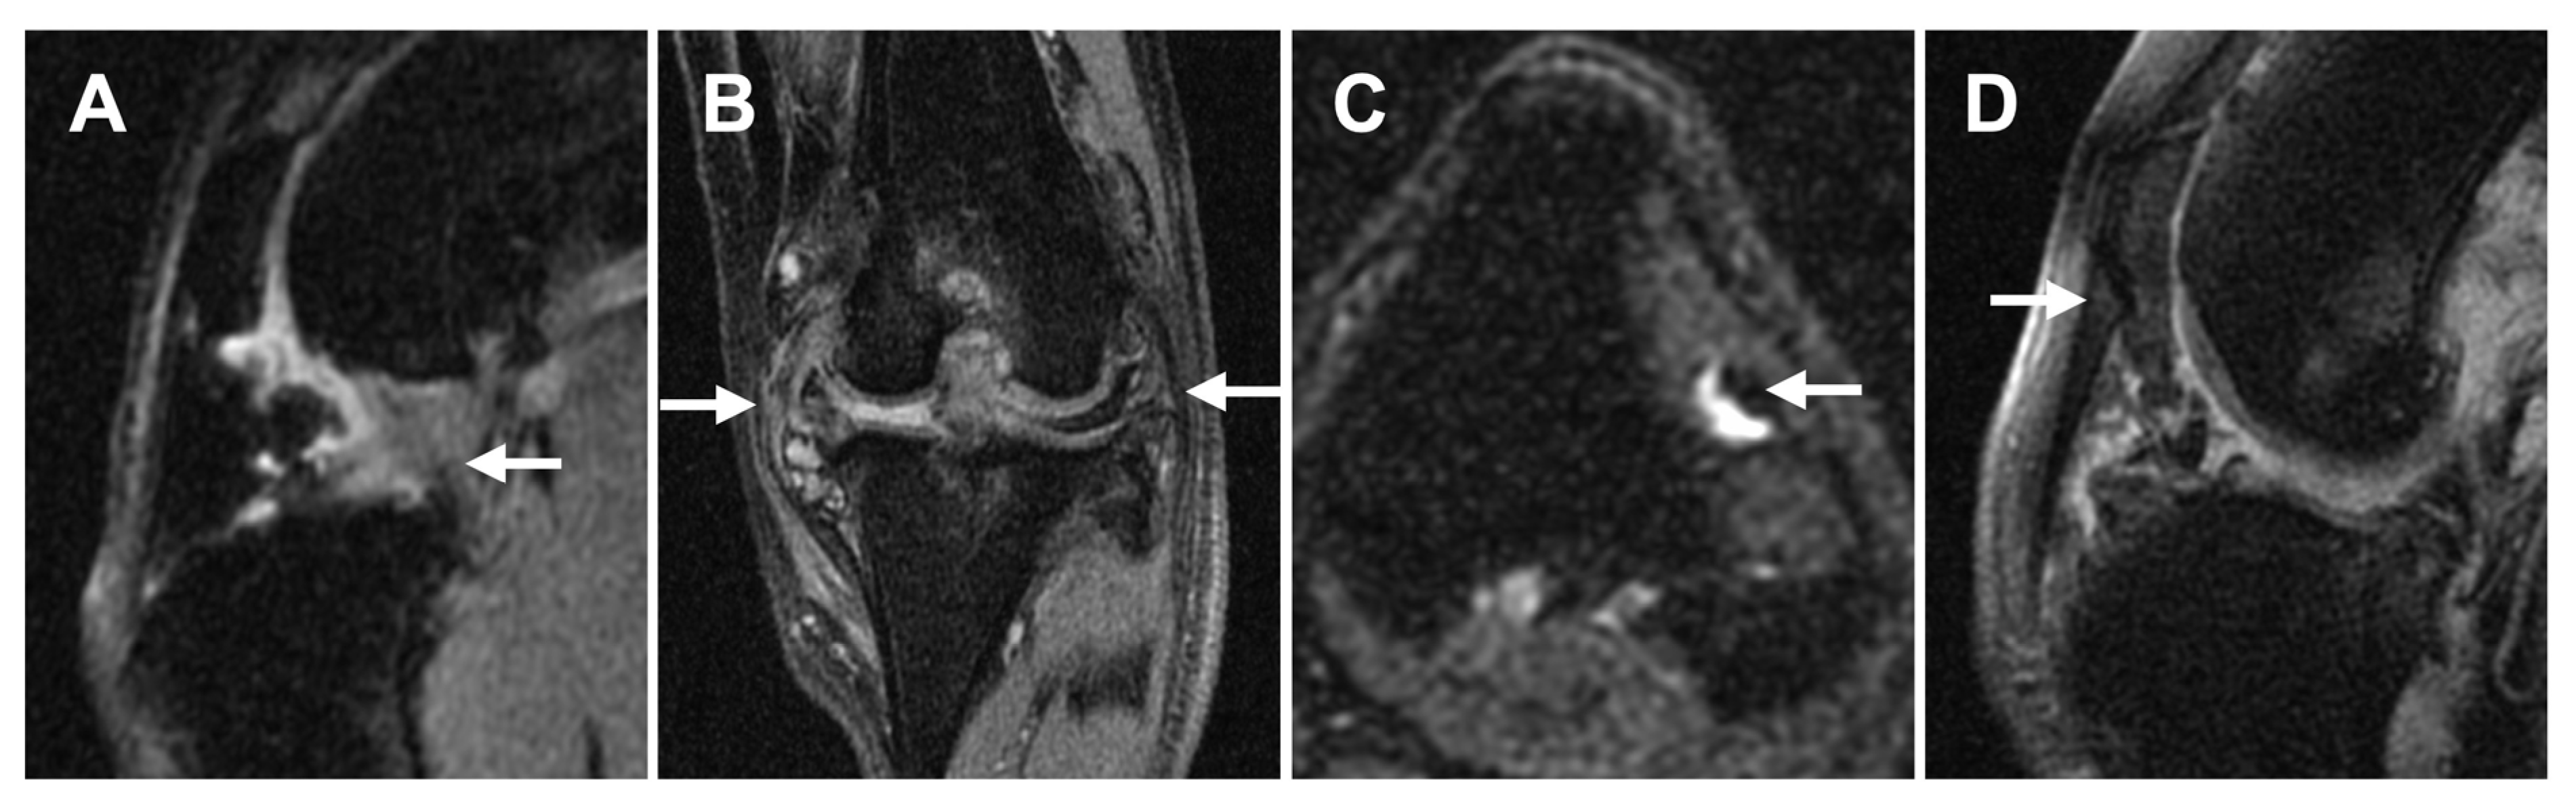

3.2.2. Ligament/Tendon Lesions

3.2.3. Synovial Effusion and Membrane Thickening